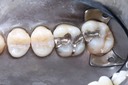

Photos of Clinical Operations

Drs. Peter Kearney, Terry McKay, John St. Germain, and Laurie Vanzella - Mentors